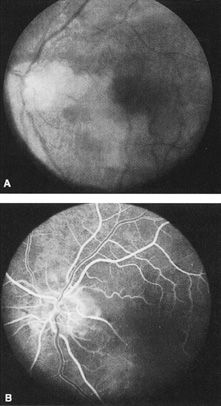

When a branch retinal artery is obstructed, there is usually whitening of the retina in the area supplied by the artery (Fig. 2). In most eyes (62% in one series), emboli are responsible for the obstruction.94 The temporal branch arteries are involved in almost all cases that have been reported,92,94 but whether this is because nasal branch retinal artery obstructions are rare or because such obstructions are simply asymptomatic is unknown. The characteristics of a branch retinal artery obstruction on intravenous fluorescein angiography are similar to those for central retinal artery obstruction.

Fig. 2. Multiple branch retinal artery obstructions in a young woman with encephalopathy and hearing loss. (Photograph courtesy of Jack W. Pierce, M.D.)

Occasionally, patients present with a bilateral branch retinal artery obstruction.94 Some have obstructive retinal arteries without evidence of systemic abnormalities,95,96 whereas others have accompanying symptoms such as deafness.97,98 Some younger patients—usually women—have been reported to have an idiopathic syndrome of branch retinal artery obstruction, encephalopathy, and hearing loss (Susac syndrome).99–104,406 The eyes on these patients are characterized by significant systemic thromboembolic events; recurrent bilateral retinal arterial occlusions; segmental arteriolar staining by fluorescein angiography, occasionally associated with periarteriolar retinal whitening or mild vitreous cells; and a predilection for vestibuloauditory or transient sensorimotor symptoms.104 Some patients, however, present with only recurrent bilateral retinal arteriolar occlusions and never develop the associated vestibuloauditory or sensorimotor systems; whether these patients have a partial manifestation of Susac syndrome is unknown. The etiology of branch retinal artery obstruction in most cases is similar to that of central retinal artery obstruction (see Table 1). Retinal diseases (such as toxoplasmosis) can also cause branch retinal artery obstruction.